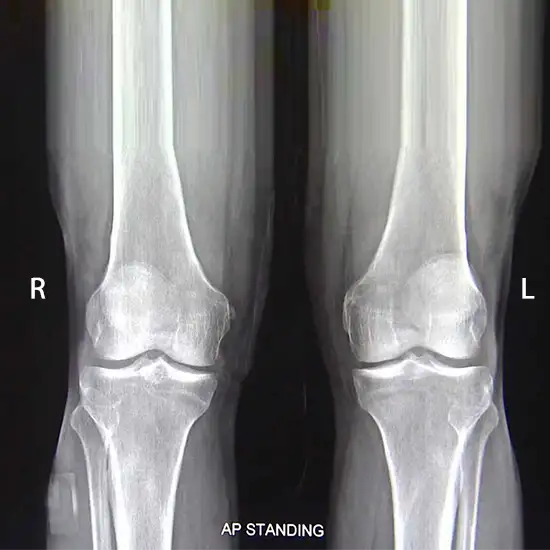

X-Ray Both Knee AP View

Knee X-rays are an imaging tool used to evaluate the knee joint's alignment, bone quality, and the number of degenerative changes. The AP view is obtained by positioning the X-ray beam in front of the patient.

Doctors recommend detecting fractures, injuries, osteoarthritis, and other knee diseases. Knee disorders typically manifest as knee pain, soreness, edema, and deformity.